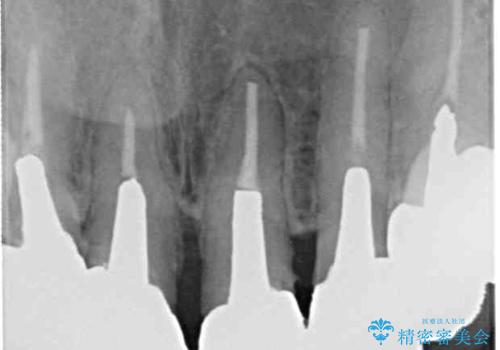

また、裏打ちに主に銀を用いた金属材料を使用するため、金属自体が黒くなったり、イオンとなり溶け出したりして、歯肉ラインが黒くなってしまうことがあります。

金属の土台を歯の色に近いものへと変更した上で、オールセラミッククラウンにて補綴することとしました。